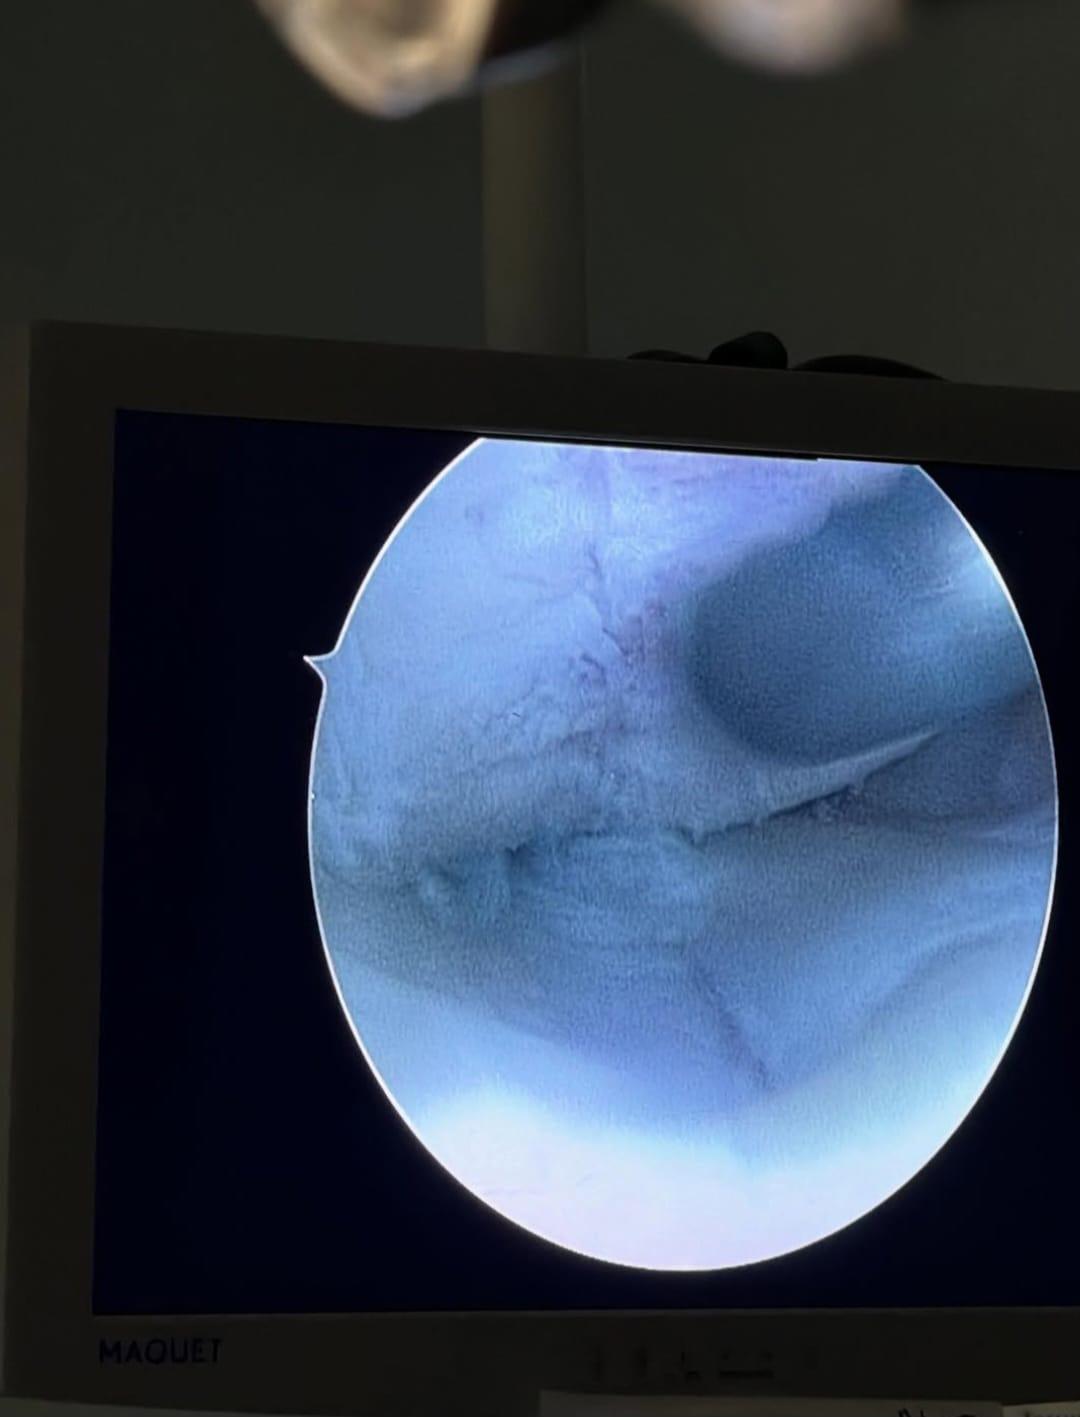

Además, Fujiyama compartió un video resumen de lo que fue su cirugía. Durante la grabación se observa cómo le realizan algunos agujeros en el hueso para hacer microfracturas que ayudarán a generar nuevos tejidos de cartilago, y así reparar la lesión. En su descripción, asegura que es un método muy nuevo, pero especial para deportistas.